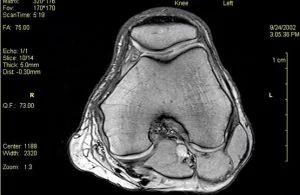

4. Fiz uma Ressonância do Joelho e, no laudo consta que tenho condromálacia patelar. Este exame é suficiente para meu diagnóstico?

MITO!

Desequilíbrios musculares e distúrbios biomecânicos estão intimamente ligados à origem da doença. Na ressonância, é muito comum imagens de degeneração da cartilagem, mas muitas vezes trata-se do envelhecimento fisiológico da cartilagem e a dor do paciente está em outro ponto do joelho.

Por isso, o diagnóstico de condromalácia patelar tem que ser dado pro médico que esteja familiarizado com o gesto esportivo que o paciente pratica. Após análise biomecânica, observando-se força excêntrica e sincronismo muscular, o médico deve observar as imagens de perda de cartilagem da patela e confrontá-las com o ponto de dor do paciente. Infelizmente, hoje muitos pacientes têm diagnostico de condromalácia patelar, quando na verdade, a lesão trata-se de uma tendinite patelar, hoffite ou plica sinovial inflamada.